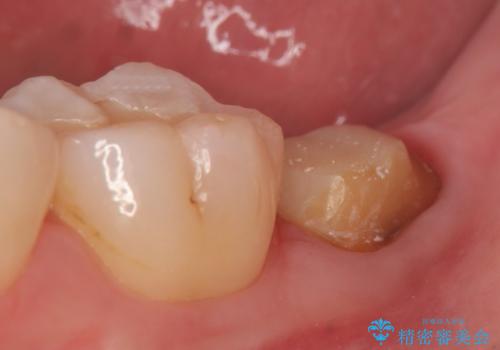

- 左下の一番奥の歯が時折激しく痛むので診て欲しいといらっしゃった方の症例です。以前に他院を受診したところ、そもそも被せ物を入れるスペースがないため抜歯しかないと言われたとのことでした。

診査の結果根尖病変を認めたため再根管治療を行った後に、被せ物を入れるスペースを作るため歯冠延長術を行いました。

歯冠延長術について

歯冠長延長術とは歯肉弁根尖側移動術とも言い、歯の高さが低くクラウン(被せ物)による治療が難しい場合に、歯茎を歯根方向に下げることで歯の高さを確保する手術です。歯の高さが十分にあることで、外れにくいしっかりとしたクラウンを被せることができます。